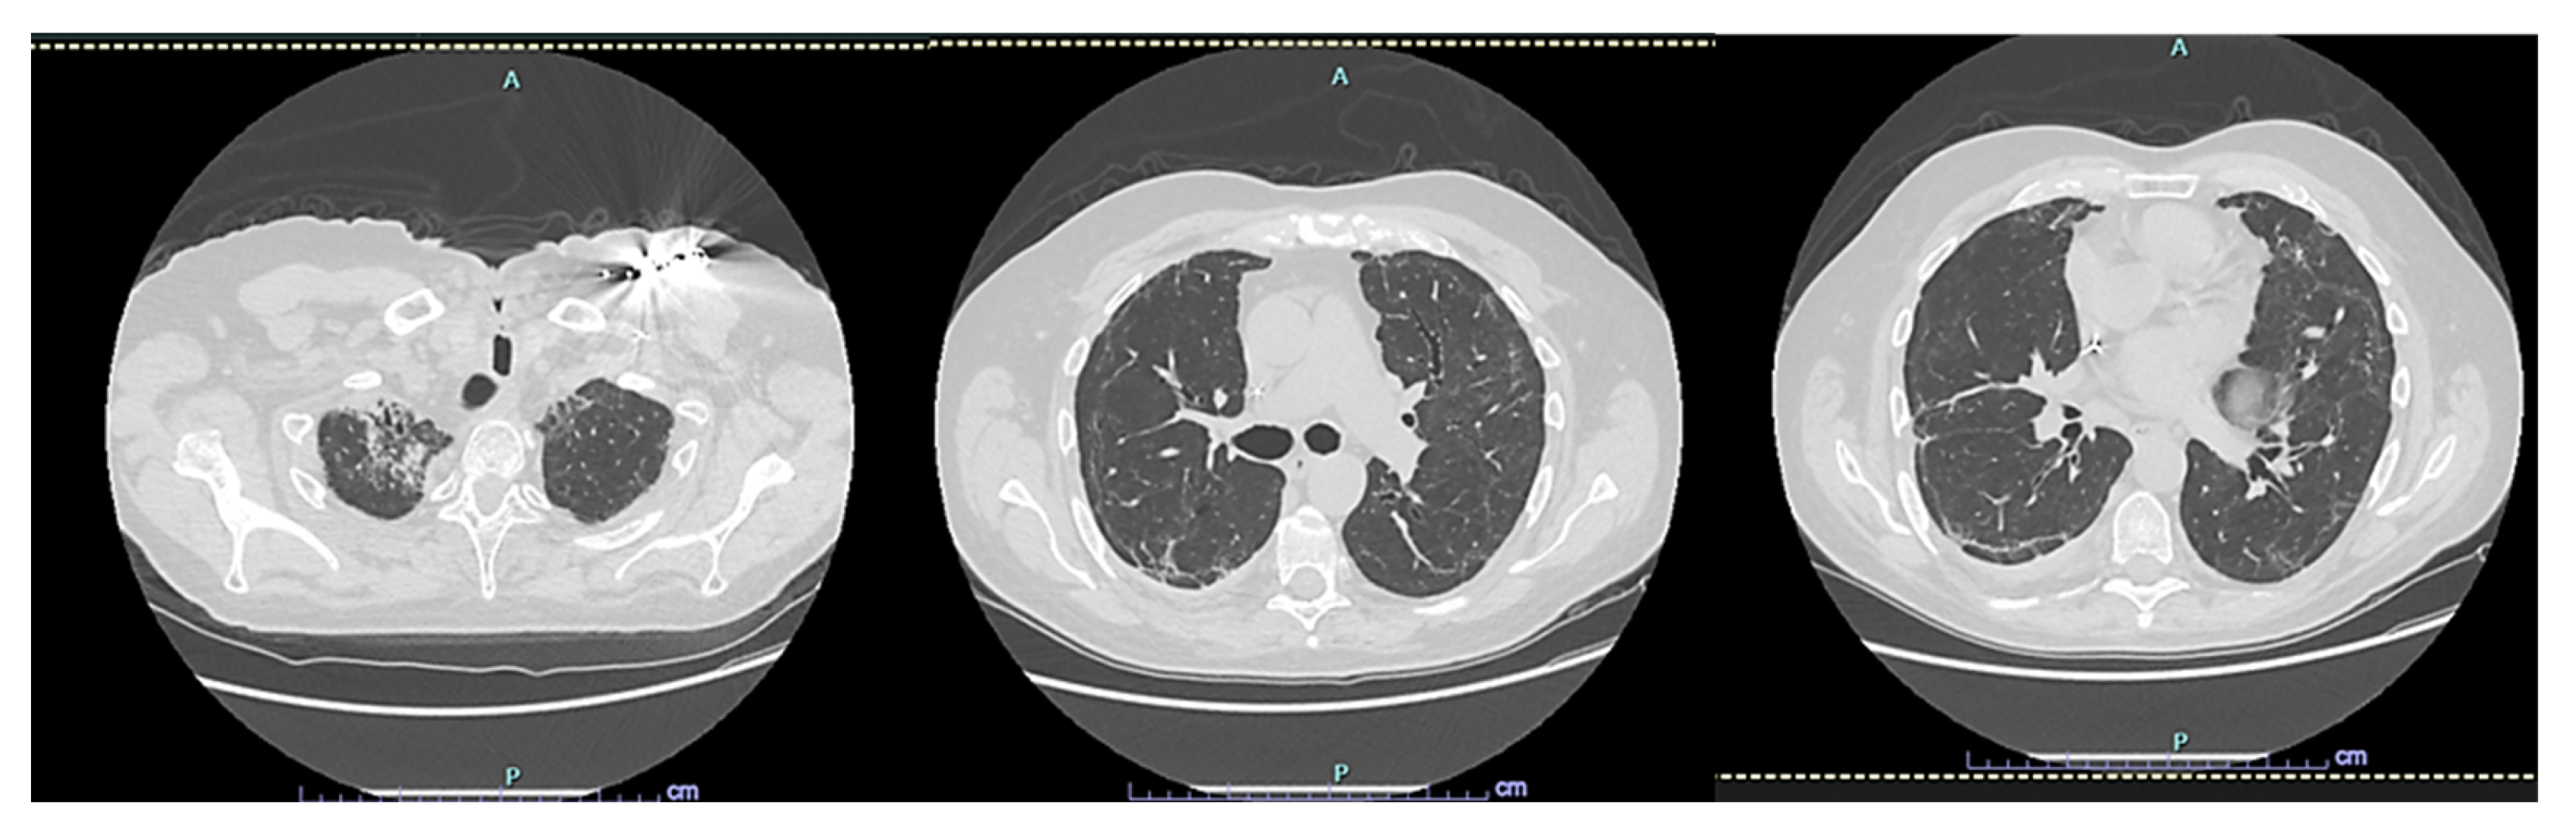

2. Case Presentation